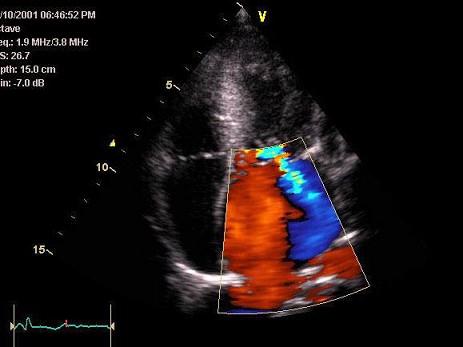

问题 如图,初步超声诊断为?(?)

选项 A.肺动脉瓣返流 B.三尖瓣返流 C.主动脉瓣返流 D.二尖瓣返流 E.肺静脉血流

答案 D